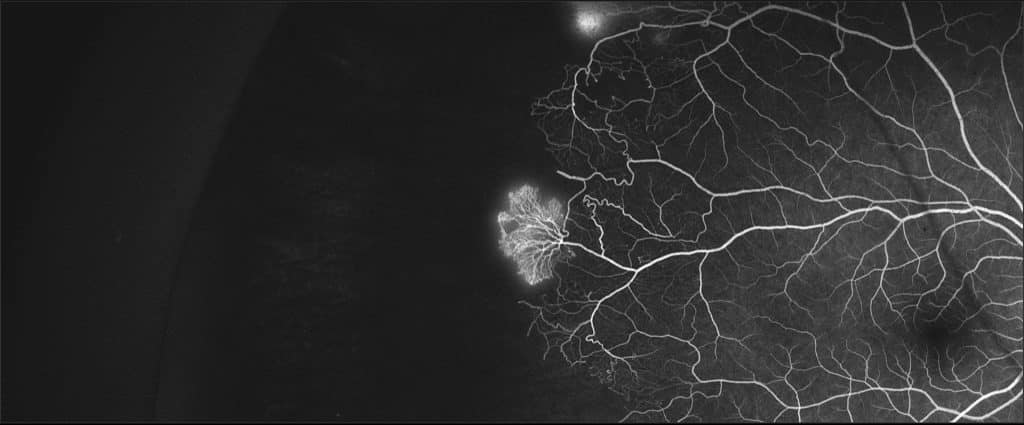

La drepanocitosi o anèmia de les cèl·lules falciformes es un trastorn genètic autosòmic recessiu importat. Aquesta patologia provoca, entre d’altres, alteracions a la vascularització perifèrica, amb una incidència del 40% segons les series clàssiques. Presentem una sèrie de 14 casos, amb una mitjana d’edat de 21 anys, on l’angiografia de camp ampli (WF-AGF) mostra una afectació del 100% dels pacients. Si bé la isquèmia es la troballa més freqüent (100%), els shunts (62,5%) i els neovasos (37,5%) també hi son present. La WF-AGF es fonamental a l’hora de valorar els pacients afectats per drepanocitosi.

A la província de Girona tenim la major presència de drepanocitosi d’Espanya, com a conseqüència de la migració de població procedent del Senegal i de Gàmbia. Aquesta recopilació, prèvia a la COVID-19, pretén ajudar a la difusió de la patologia i a millorar-ne l’estudi. Malauradament, els interessos econòmics del primer món no se centren en aquesta patologia i els estudis científics daten del segle passat. Cal més recerca.